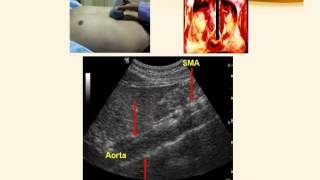

• Cara membaca hasil USG abdomen

Prosedur USG abdomen adalah upper lower abdome jejum Abdominal nedir ne demek and scrotum Preparo total perut atas Persiapan Apakah perlu puasa ...